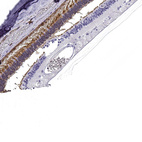

Immunohistochemical staining of human retina shows strong cytoplasmic positivity in rods.